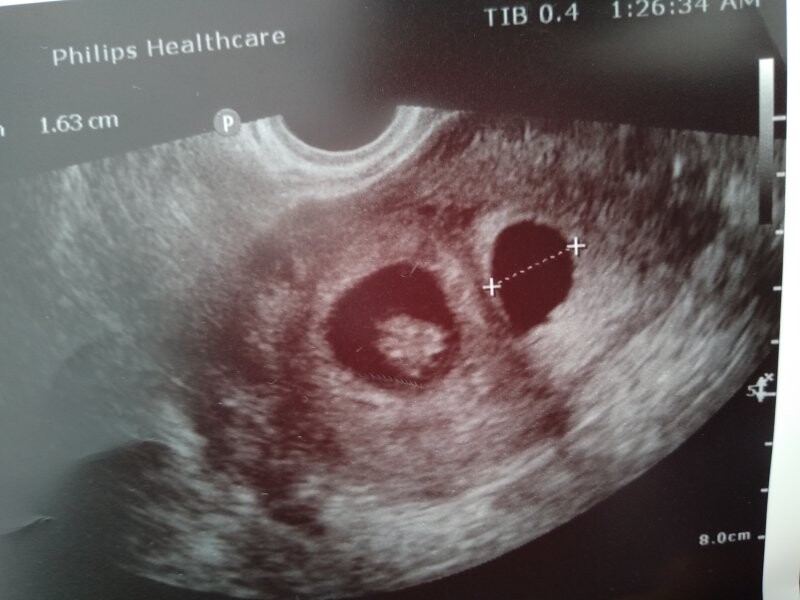

Dobrý denKolik dní to je podle velikosti reálné po ovulaci?Děkuji

Dobrý den,

jedná se o velmi časnou fázi těhotenství, přesně stáří Vám takto nelze říct, nicméně vzhledově embryo odpovídá cca 6.-7. gestačnímu týdnu.